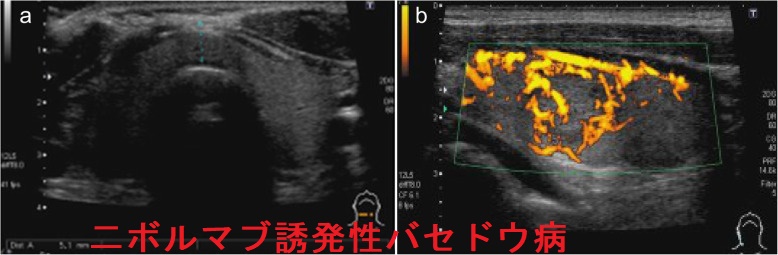

ニボルマブ(商品名:オプジーボ)でバセドウ病が発症

イタリアにあるピサ大学の報告では、TSH受容体自己抗体(TRAb)陰性の甲状腺中毒症であっても、甲状腺中毒期の持続性、甲状腺超音波(エコー)検査での血流増加、甲状腺シンチグラフィーでの取り込み(集積)増加を認めたため、ニボルマブ誘発性甲状腺機能亢進症/バセドウ病と確定診断したそうです。メチマゾール(日本ではメルカゾール®)投与で速やかに甲状腺機能正常化。(Eur Thyroid J. 2019 Jul;8(4):192-195.)